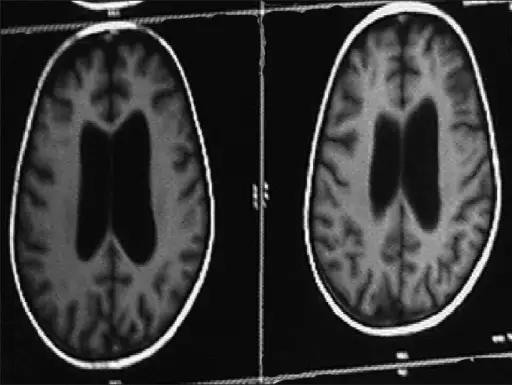

Rarely, the mumps can lead to life-threatening side effects such as:

- Brain infection